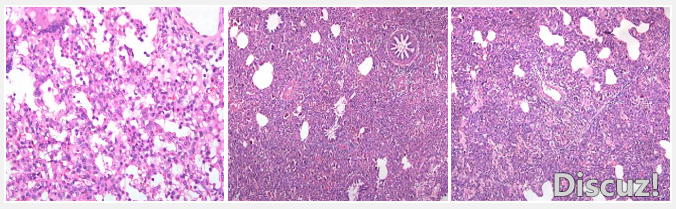

藍(lán)耳病,動(dòng)脈炎屬,病毒1991年被分離。即使在科技迅速發(fā)展的今天,藍(lán)耳病仍然能帶來(lái)無(wú)法估量的損失。 發(fā)病機(jī)理-肺巨噬系統(tǒng)的重要性 作為免疫抑制疾病的代表,藍(lán)耳病毒主要是攻擊全身的巨噬細(xì)胞系統(tǒng)。巨噬細(xì)胞系統(tǒng) ...